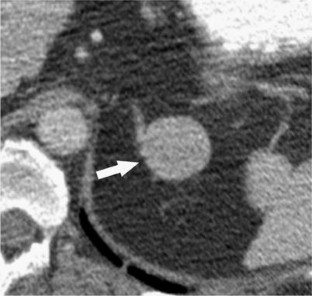

Benign OANs were smaller [mean size 3.7 cm (range 2.6–5.3)] and more homogeneous than malignant OANs and demonstrated greater washout [mean washout percentage 72.3% (range 61–88)]. Malignant OANs demonstrated features similar to ACCs, including size [mean 9.4 cm (range 5.2–9.8)] and internal necrosis (n = 6). Mean enhancement washout percentage for malignant OANs was 12% (range −8 to 32).

Benign OANs (oncocytomas) may be distinguished from lipid-rich adenomas on non-contrast CT but may be indistinguishable from lipid-poor adenomas. Malignant oncocytic neoplasms can demonstrate features similar to ACCs, including larger size, internal necrosis, and lower percentage enhancement washout.